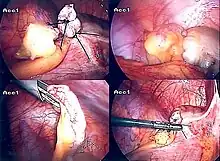

The surgical procedure for the removal of the appendix is called an appendectomy. Appendectomy can be performed through open or laparoscopic surgery. Laparoscopic appendectomy has several advantages over open appendectomy as an intervention for acute appendicitis.[84]

Laparoscopic appendectomy

Laparoscopic appendectomy was introduced in 1983 and has become an increasingly prevalent intervention for acute appendicitis.[88] This surgical procedure consists of making three to four incisions in the abdomen, each 0.25 to 0.5 inches (6.4 to 12.7 mm) long. This type of appendectomy is made by inserting a special surgical tool called a laparoscope into one of the incisions. The laparoscope is connected to a monitor outside the person's body, and it is designed to help the surgeon to inspect the infected area in the abdomen. The other two incisions are made for the specific removal of the appendix by using surgical instruments. Laparoscopic surgery requires general anesthesia, and it can last up to two hours. Laparoscopic appendectomy has several advantages over open appendectomy, including a shorter post-operative recovery, less post-operative pain, and lower superficial surgical site infection rate. However, the occurrence of an intra-abdominal abscess is almost three times more prevalent in laparoscopic appendectomy than open appendectomy.[89]